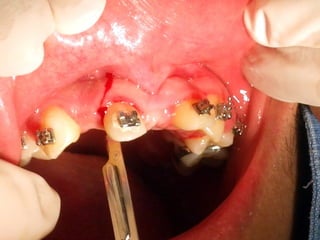

Mini-implantes para apoyo de fuerzas ortodóncicas

Mini-implantes para apoyode fuerzas ortodóncicas